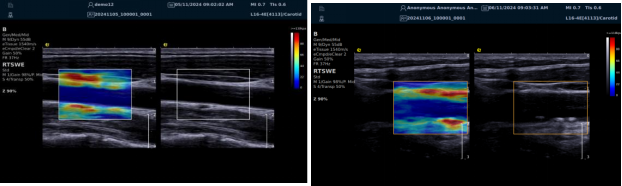

image.png

? 显著提高对低速血流的敏感度,实现高分辨率、高帧频实时微血流成像(分辨率 30 微米、帧频 150 /s),动态显示斑块内新生血管血流。

? 基于多普勒原理进行频谱测量与 VI 指数计算,定量评估斑块内新生血管。

? 成像质量接近造影效果且无需造影剂,无创简便,增强诊断准确性,适用于细微血流变化场景。